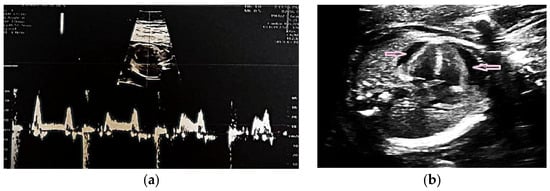

Interests: molecular, ultrasound and clinical characterization of pregnancy complications; placental histology

Interests: perinatal ultrasound; serum markers for complications of pregnancy; histopathology of the placenta; neonatal pathological conditions

- ultrasound